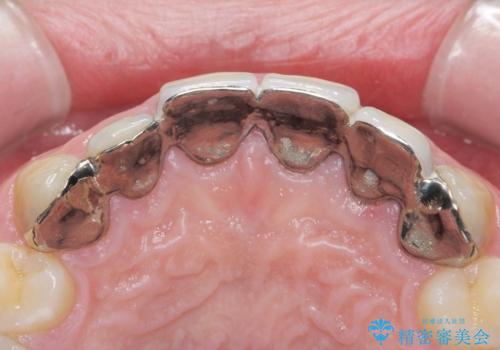

前歯には接着性の維持装置や、中途半端な形の連結クラウンが装着され、清掃性が悪く歯ぐきの腫れや、歯ぐきの形態の不揃いが認められました。

ただ、白いオールセラミッククラウンを製作・装着するのではなく、将来にわたり安定した状況を獲得するため、歯周外科を行い歯ぐきと周囲の歯槽骨の形態を整えていきます。